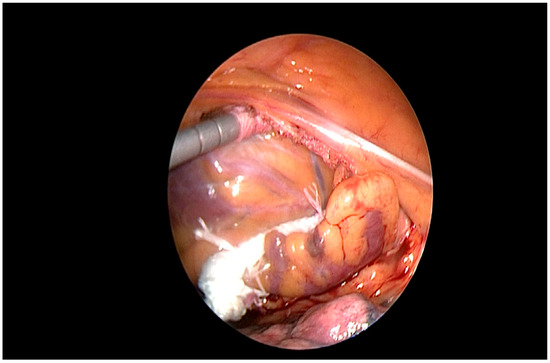

2.7. Procedure

- Branzoli, S.; Marini, M.; Guarracini, F.; Pederzolli, C.; D’onghia, G.; Centonze, M.; Pomarolli, C.; Graffigna, A.; La Meir, M. Stand alone totally thoracoscopic left appendage clipping: Safe simple standardized. Ann. Thor. Surg. 2021, 111, e61–e63. [Google Scholar] [CrossRef]

- Branzoli, S.; Guarracini, F.; Marini, M.; D’onghia, G.; Catanzariti, D.; Merola, E.; Annicchiarico, L.; Casagranda, G.; Stegagno, C.; Fantinel, M.; et al. Heart team for left appendage occlusion without the use of antithrombotic therapy: The epicardial perspective. J. Clin. Med. 2022, 11, 6492. [Google Scholar] [CrossRef]